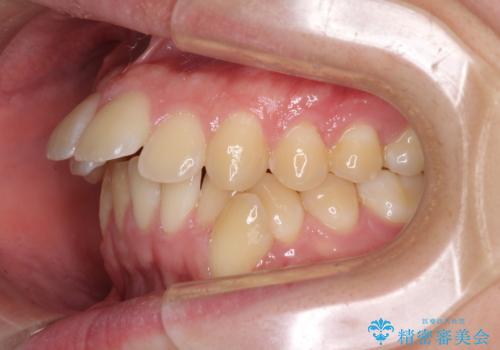

出っ歯と八重歯 目立たない裏側装置でスッキリとした口元に

- 上顎の前突感による口の閉じにくさと八重歯を気にして来院された患者様です。

下顎骨が左側に大きく変位しているため、上下の正中位置は極力一致するところをゴールとしました。

上下顎で左右差の大きい抜歯矯正を裏側装置で行ったため、非常に時間がかかりましたが、正中位置も良い位置に改善され、気になっていた突出感も解消されました。